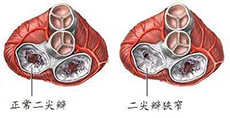

心脏瓣膜病及其他疾病

疾病介绍:心脏瓣膜病及其他疾病心脏瓣膜病就是指二尖瓣、三尖瓣、主动脉瓣和肺动脉瓣的瓣膜因风湿热、黏液变性、退行性改变、先天性畸形、缺血性坏死、感染或创…【详细】

心脏瓣膜病及其他疾病

疾病介绍:心脏瓣膜病及其他疾病心脏瓣膜病就是指二尖瓣、三尖瓣、主动脉瓣和肺动脉瓣的瓣膜因风湿热、黏液变性、退行性改变、先天性畸形、缺血性坏死、感染或创…【详细】

心脏瓣膜病及其他疾病

疾病介绍:心脏瓣膜病及其他疾病心脏瓣膜病就是指二尖瓣、三尖瓣、主动脉瓣和肺动脉瓣的瓣膜因风湿热、黏液变性、退行性改变、先天性畸形、缺血性坏死、感染或创…【详细】

心脏瓣膜病及其他疾病

疾病介绍:心脏瓣膜病及其他疾病心脏瓣膜病就是指二尖瓣、三尖瓣、主动脉瓣和肺动脉瓣的瓣膜因风湿热、黏液变性、退行性改变、先天性畸形、缺血性坏死、感染或创…【详细】

心脏瓣膜病及其他疾病

疾病介绍:心脏瓣膜病及其他疾病心脏瓣膜病就是指二尖瓣、三尖瓣、主动脉瓣和肺动脉瓣的瓣膜因风湿热、黏液变性、退行性改变、先天性畸形、缺血性坏死、感染或创…【详细】

心脏瓣膜病及其他疾病

疾病介绍:心脏瓣膜病及其他疾病心脏瓣膜病就是指二尖瓣、三尖瓣、主动脉瓣和肺动脉瓣的瓣膜因风湿热、黏液变性、退行性改变、先天性畸形、缺血性坏死、感染或创…【详细】

心脏瓣膜病及其他疾病

疾病介绍:心脏瓣膜病及其他疾病心脏瓣膜病就是指二尖瓣、三尖瓣、主动脉瓣和肺动脉瓣的瓣膜因风湿热、黏液变性、退行性改变、先天性畸形、缺血性坏死、感染或创…【详细】